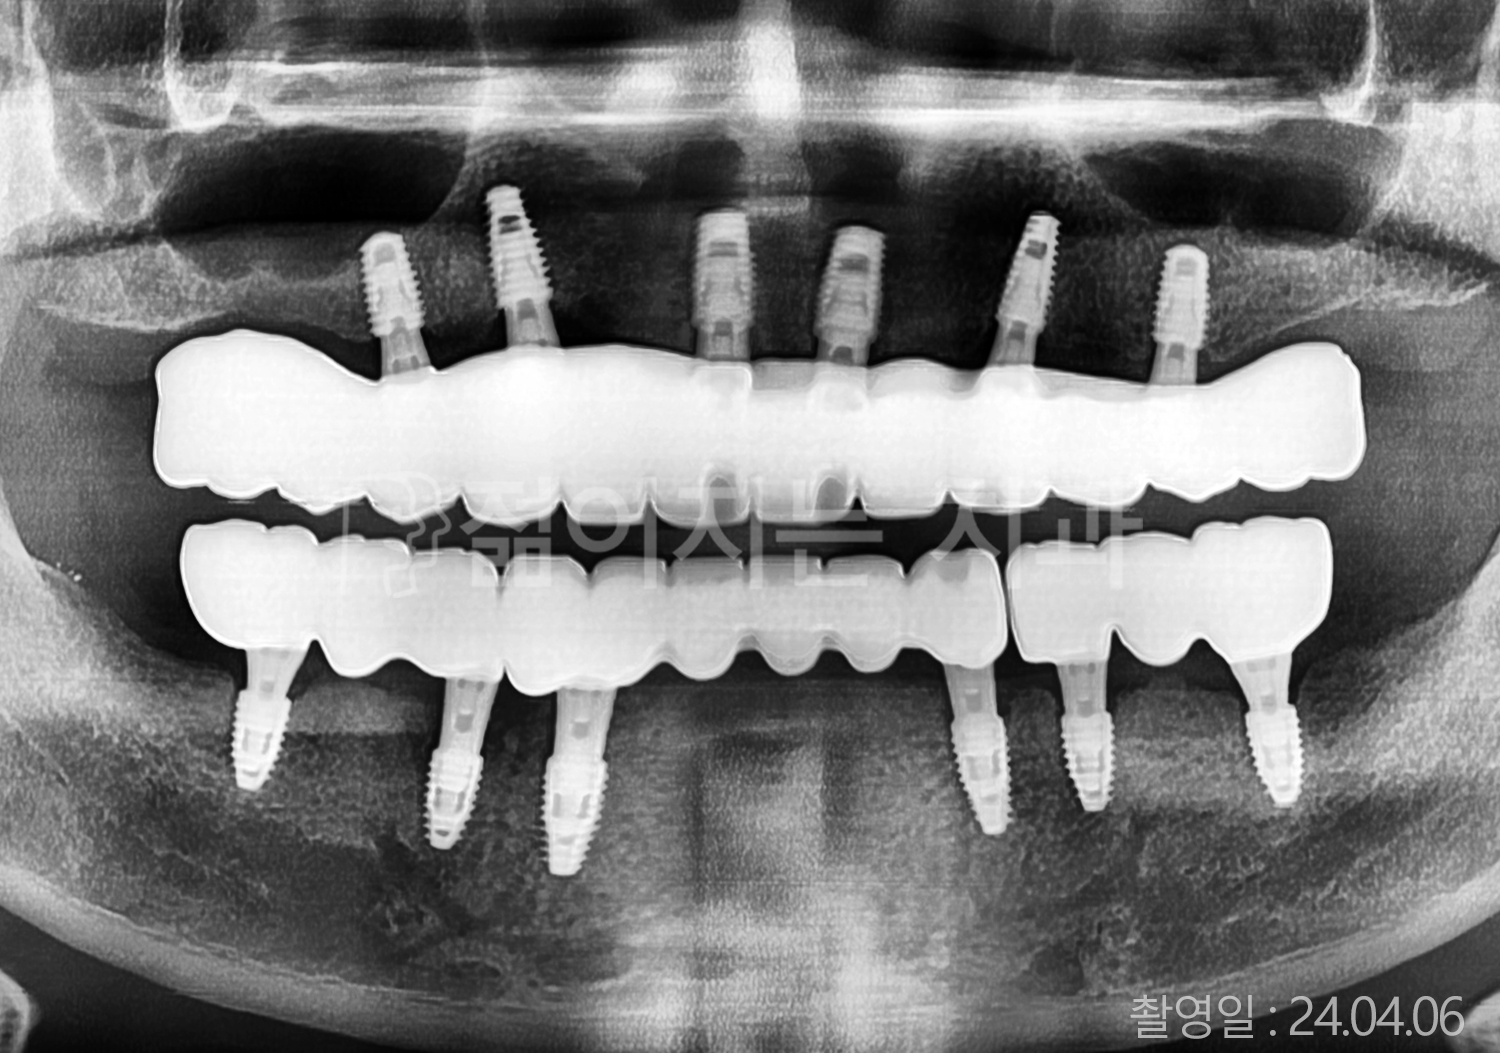

• 50대 전체치아 10개 이상 임플란트